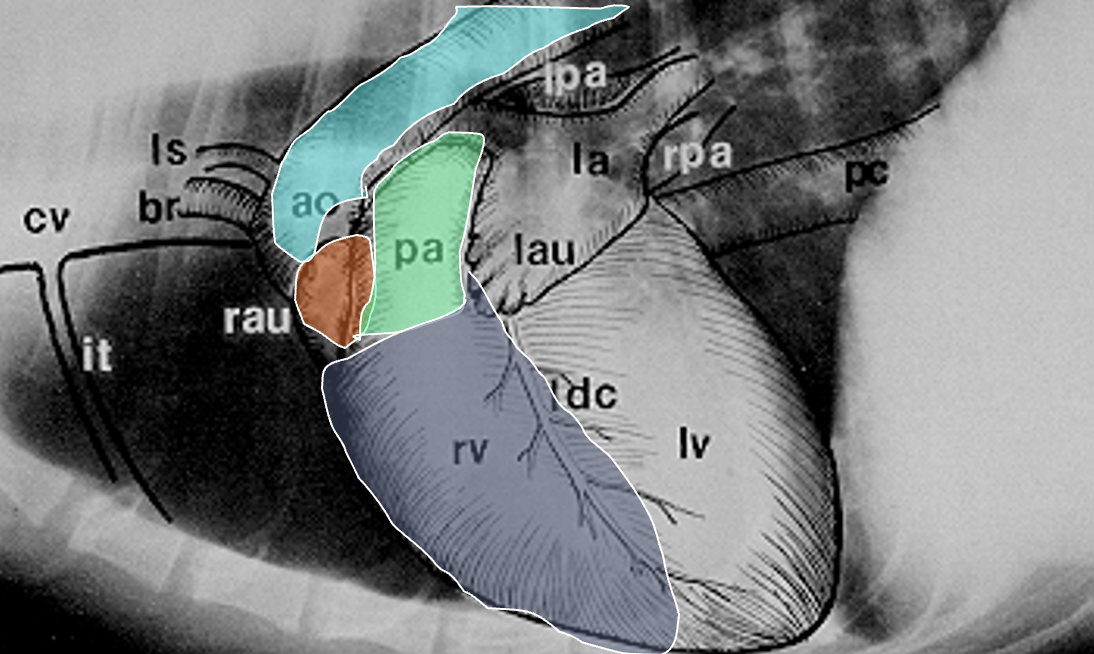

Which structures are outlined in this image?

light blue: ascending aorta

mint: main pulmonary artery

orange: right auricle

dark blue: right ventricle